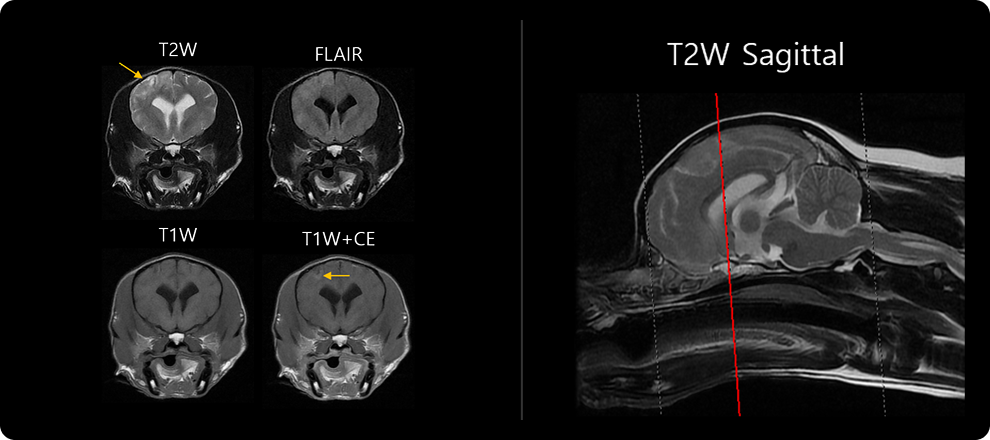

· MRI 검사

MRI 검사는 다양한 촬영 기법을 이용해 뇌질환을 감별하는 검사입니다. 뇌수막염에서는 뇌 부종성 병변, 괴사 병변, 뇌수막 변성 및 조영 증강, BBB(뇌혈관장벽) 손상 여부를 중점적으로 확인합니다. 이 단계에서 뇌와 척수의 구조적 이상, 염증의 위치와 범위를 파악합니다. 앞서 진행한 병력 청취 및 신경계 검사를 바탕으로 촬영 부위를 설정하며, 부위는 두개, 경추, 흉요추, 요천추 등으로 나뉩니다.

1-1 1-2 1-2 1-2

당연하게도 마비, 경련, 의식 저하 등의 초기 증상이 경등도이고, MRI 상 병변의 분포 범위 및 정도가 약한 환자, 조영제 누출 등 뇌수막의 병변이 제한적인 환자 등에서는 임상 경과가 양호한 경향을 보일 수 있습니다. 스테로이드 처방 역시 중증의 병변을 보이는 환자들에 비해 적게 사용할 수 있는 경향들이 있습니다. 초기 3개월간의 치료 경과가 양호한 환자의 경우 장기 생존율이 높은 경향을 보이기도 합니다.